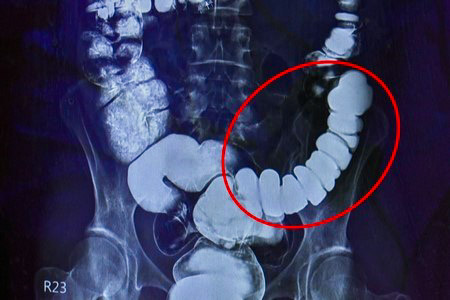

右圖:大腸可說是人體的第二個大腦,腸子緊繃,表示情緒壓力反應在腸道上,易造成便祕。

經過大腸攝影檢查,邱建銘主任發現腸子繃得非常緊,這是典型情緒影響腸道的病例,臨床不算少,但邱主任仍不免驚訝:「沒看過把自己腸子逼得這麼緊的。」